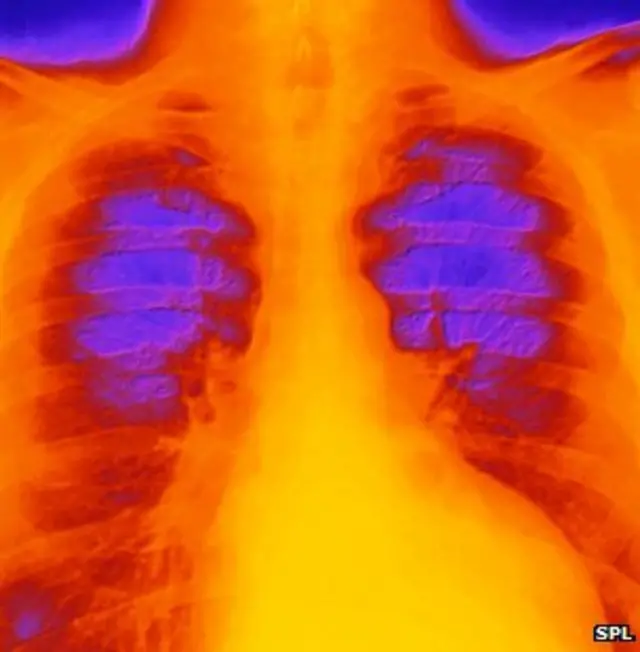

Fuente de la imagen, SPL

Corazón aturdido

Algunas personas hablan de "síndrome de corazón roto", conocido más formalmente como cardiomiopatía por estrés o cardiomiopatía Takotsubo.

"Es una condición temporal en la que el músculo cardíaco se debilita repentinamente o se aturde. El ventrículo izquierdo, una de las cavidades del corazón, cambia de forma", según explican en la Fundación Británica del Corazón.

El estrés súbito hace que el ventrículo izquierdo del corazón -el que bombea la sangre- adquiera esta forma.